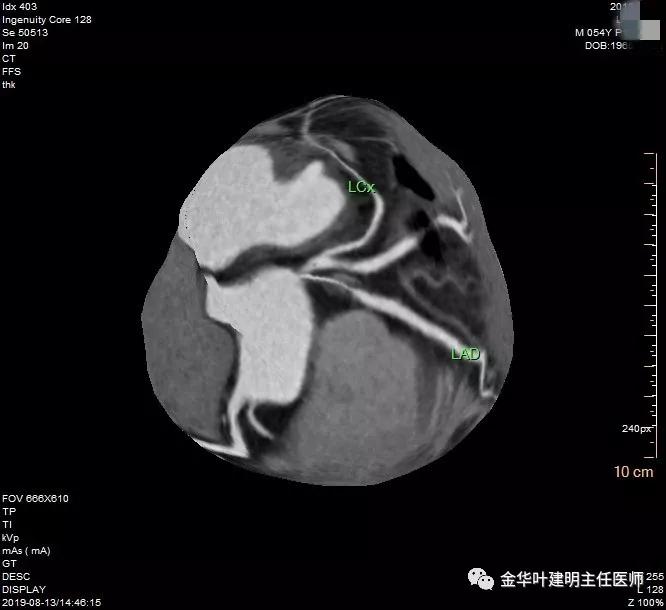

心内科予以进一步查了冠脉造影,结果如下:

可见是前降支中段60%狭窄,那么还不至于需要支架植入或搭桥的程度,予以口服相关药物后就出院了。